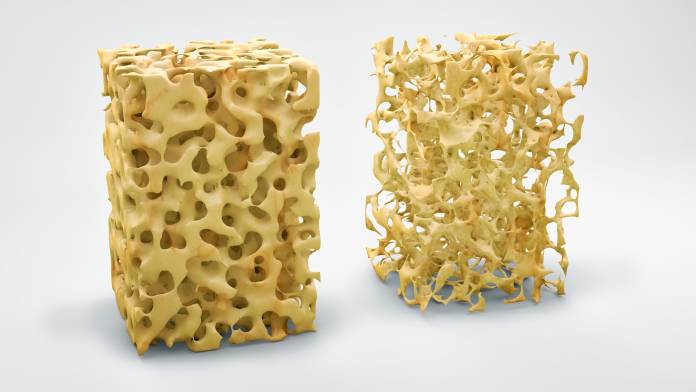

Osteoporose

OsteoporoseDie Osteoporose ist eine Erkrankung, bei der es wegen einer Abnahme der Knochensubstanz zur verminderten Stabilität der Knochen kommt. Sie …